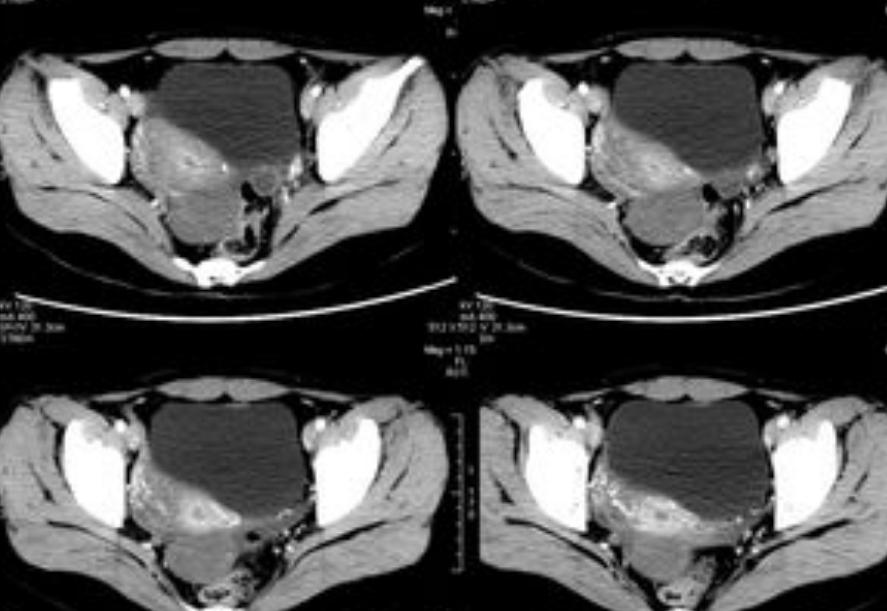

经过各项检查,其余指标均正常,但盆腔及乳腺B超显示双侧卵巢偏小,根据患者的病史、症状以及相关检查,可初步考虑患者为卵巢早衰。